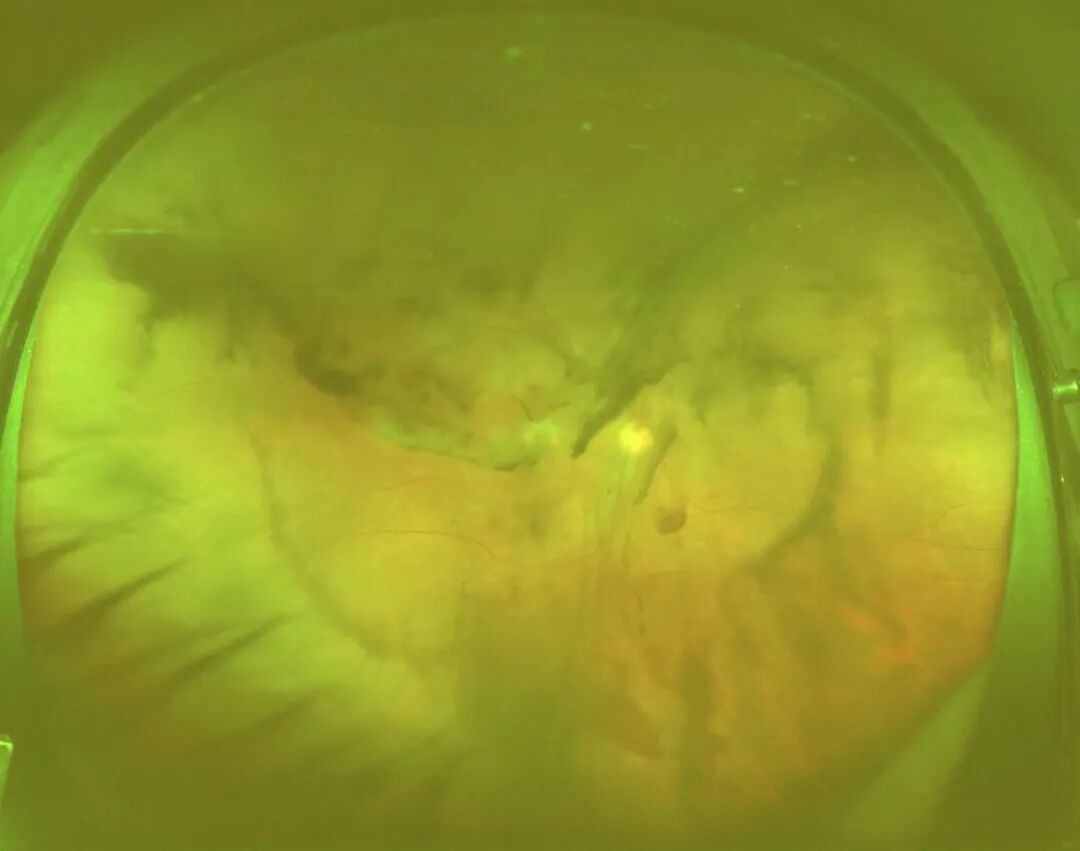

封亮旗主任询问了王先生的病史,得知王先生是一名2型糖尿病患者。结合王先生的病情症状,封主任为他安排了全面的眼部检查,其中报告显示王先生的右眼视力为0.25,眼内有大量出血,且黄斑区水肿、增厚,确诊王先生是眼底出血和黄斑水肿,属于视网膜病变的一种。而究其原因,是由糖尿病引起的眼底并发症。

▲王先生右眼眼底检查图片